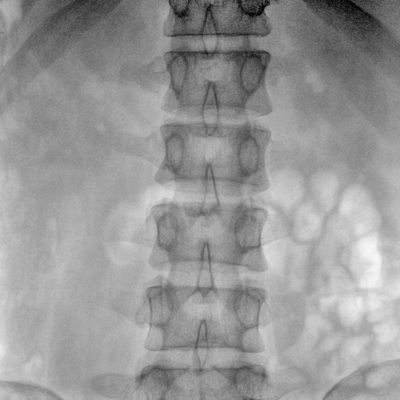

大尺寸動態(tài)平板探測器,高DQE、低噪聲、圖像清晰。采用多分辨率圖像增強處理技術(shù),不同部位不同圖像處理算法,滿足客戶多樣化的需求。

采用智能變頻脈沖透視技術(shù),優(yōu)化圖像質(zhì)量的同時降低輻射劑量,呵護(hù)醫(yī)患健康